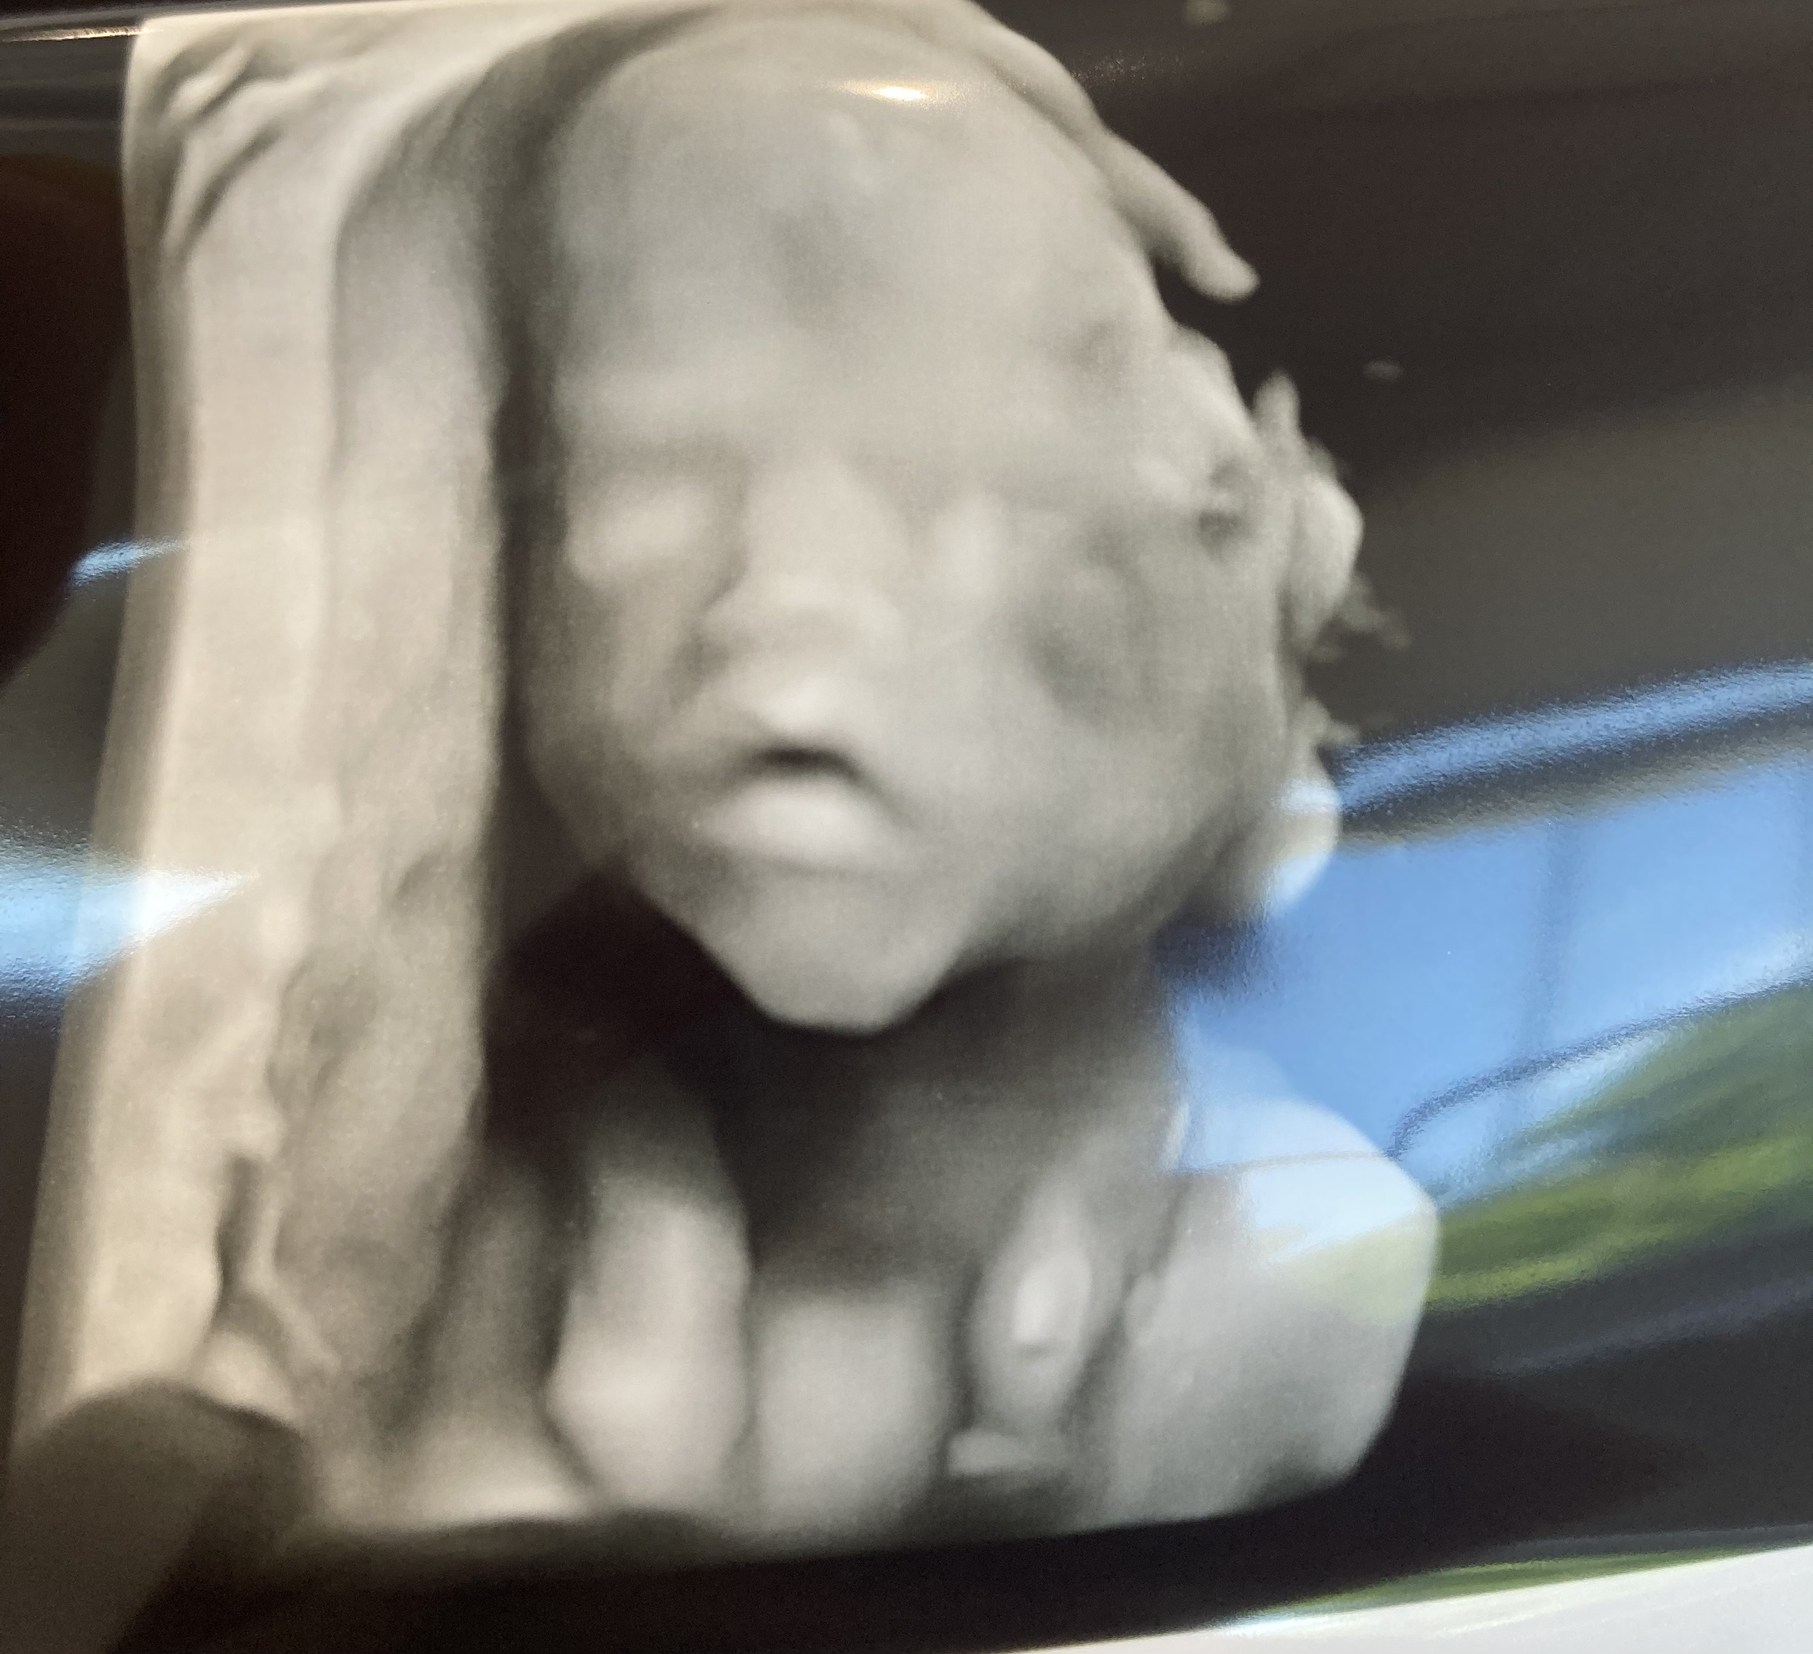

After 3 long ultrasound sessions over 3 weeks, finally got good images of everything and she is looking good in every way! Phew! She was so stubborn and mischievous which I’m not shocked about. I drank orange juice, went for walks, iced beverages, flipped around back and forth and a few sips of Coke (which I think did the trick). Here is her cute profile, sucking her thumb and little feet at 18 weeks.

I had my anatomy scan yesterday, little girl was very cooperative and everything looks perfect, she weighs 13oz. The coolest part was she did some 3d images… kinda creepy but so beautiful:)